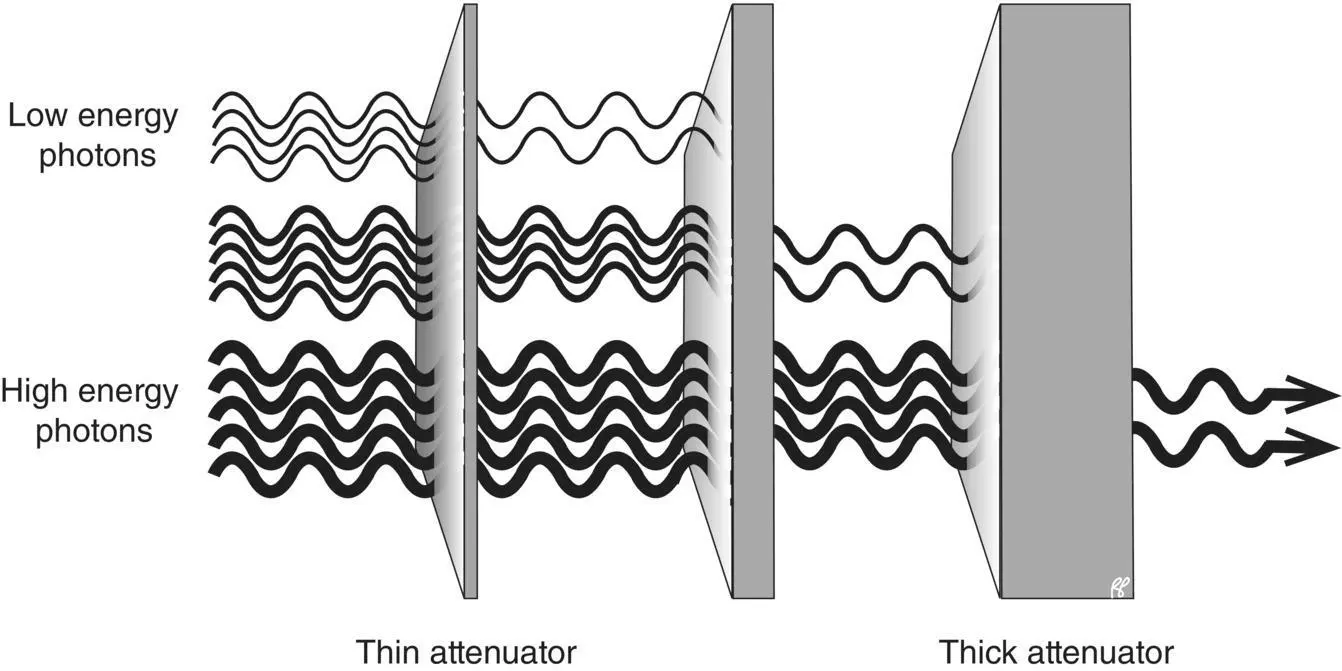

For any attenuator the HVL can be determined experimentally using a photon source and a suitable detector. For calculations involving attenuation of high‐intensity radiation beams, an entirely similar concept, the tenth‐value layer ( TVL), is useful. The TVL is the thickness of the attenuator that will transmit only one tenth of the photons in the beam. For a monoenergetic beam (containing photons of identical energies) directed at a material, two such thicknesses will transmit only one hundredth of the beam. If, however, the beam contains photons of different energies this rule is not applicable (see text box on beam hardening).

When a beam contains photons of different energies such as an X‐ray beam, it is termed polychromatic.As a polychromatic beam penetrates a material, lower energy photons are extinguished or scattered preferentially over higher energy photons and the result is that, while the overall intensity is diminished, the average energy of the transmitted fraction of the beam is increased. This phenomenon is known as beam hardening. A hardened beam is more penetrating and so a second HVL or TVL will be slightly thicker than the first.

Figure 2.6 The amount of attenuation of a photon beam is dependent on the photon energy and the thickness (and/or atomic number) of the attenuator.